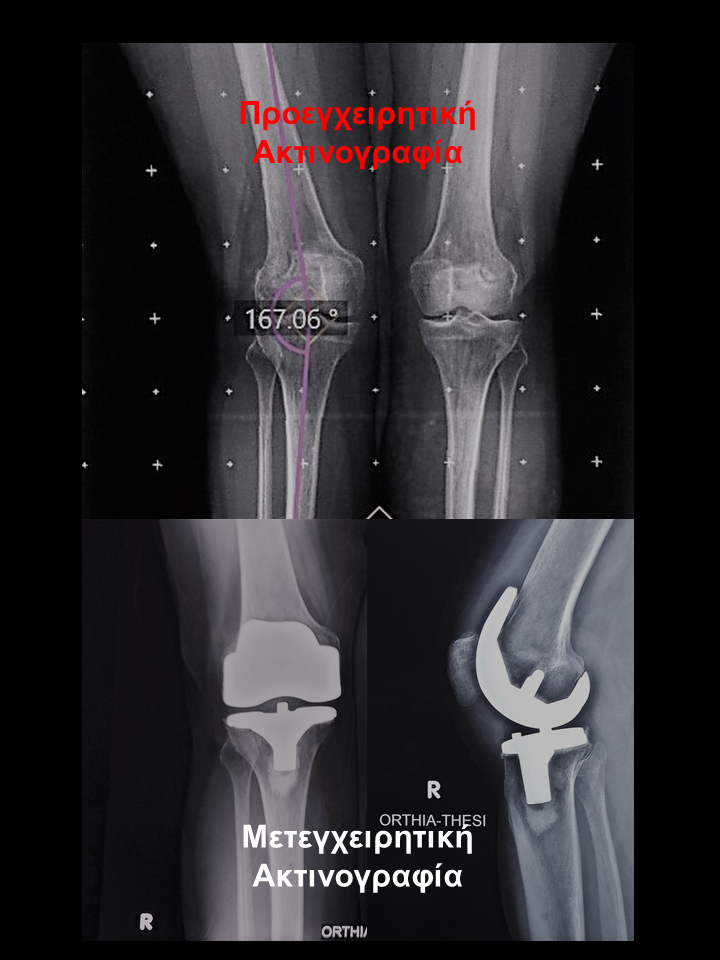

Ασθενής με οστεοαρθρίτιδα δεξιού γόνατος και μεγάλη παραμόρφωση

Ασθενής  66 χρονών με οστεοαρθρίτιδα δεξιού γόνατος, μεγάλη παραμόρφωση και επιδεινούμενο άλγος γόνατος που την δυσκόλευε στη βάδιση, στο κάθισμα και την αφυπνούσε το βράδυ. Υπεβλήθη σε ρομποτική αρθροπλαστική στο δεξί γόνατο. Χρησιμοποιήθηκε η τεχνική διατήρησης οστού όπου αφαιρέθηκαν λιγότερα χιλιοστά οστού. Ο άξονας από 100 απόκλιση και έλλειμα έκτασης 60 αποκαταστάθηκε στις 00 και το έλλειμα έκτασης – 40 . Η ασθενής βαδίζει πλέον χωρίς καμία ενόχληση.